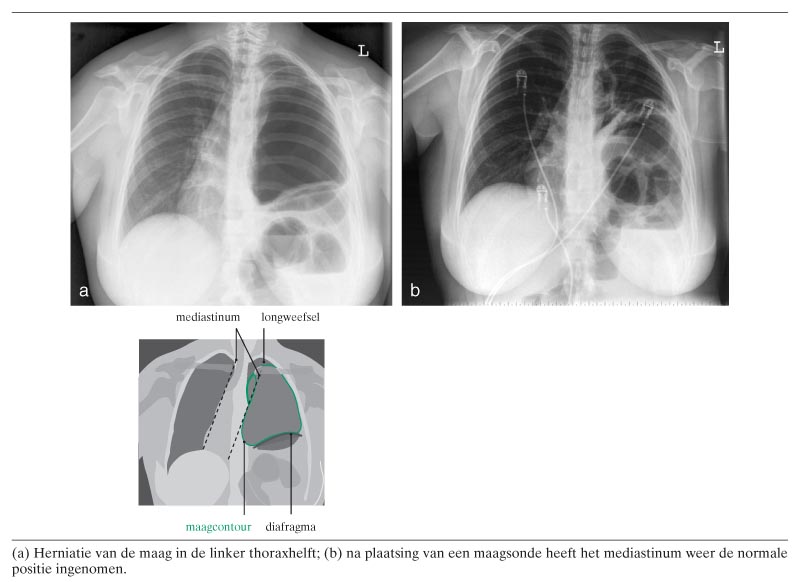

Een 20-jarige vrouw presenteerde zich met buikpijn, misselijkheid en opboeren. Op 8-jarige leeftijd had zij een Nissen-fundoplicatie ondergaan wegens gastro-oesofageale reflux. Bij lichamelijk onderzoek was er geen dyspnoe. De bloeddruk van patiënte bedroeg 140/90 mmHg, met een pols van 84/min. Bij auscultatie werd er geen ademgeruis gehoord over de linker thoraxhelft. De thoraxfoto toonde herniatie van de maag in de linker thoraxhelft met daarbij een naar craniaal verplaatst diafragma (figuur a). Bij de aanwezigheid van veel lucht in de maag was, conform een spanningspneumothorax, het mediastinum naar rechts verplaatst. Nadat een maagsonde was ingebracht voor decompressie van…